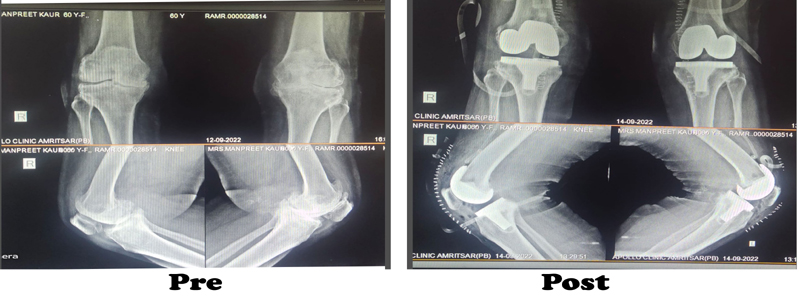

During the knee replacement surgery, the worn out surface (cartilage) of the joint is removed and is capped with implants called as endo-prosthesis. The femur and tibial sides are metal backed and in between there is polyethylene ‘insert’. The patella may or may not be replaced, depending upon the surgeon preference and condition of patellar cartilage.

The surgeon will make an incision on the top of your knee in order to expose the damaged area of your joint. The standard incision size can be as long as 10 inches, but a minimally invasive procedure can result in incisions as short as 6 inches. During the operation, the surgeon moves your kneecap aside and cuts away damaged bone and cartilage, which are then replaced with new metal and plastic components. The components combine to form a synthetic (but biologically compatible) joint that mimics the movement of your natural knee. Most knee replacement procedures take 30min - 1 hour to complete.

Recent advances in the form of minimal invasive (small cut) surgery, knees with high flex joints where one can still cross legs, joints that lasts longer, lesser blood loss, early recovery and holistic patient care, are the things which is offered to you by his team under his leadership.